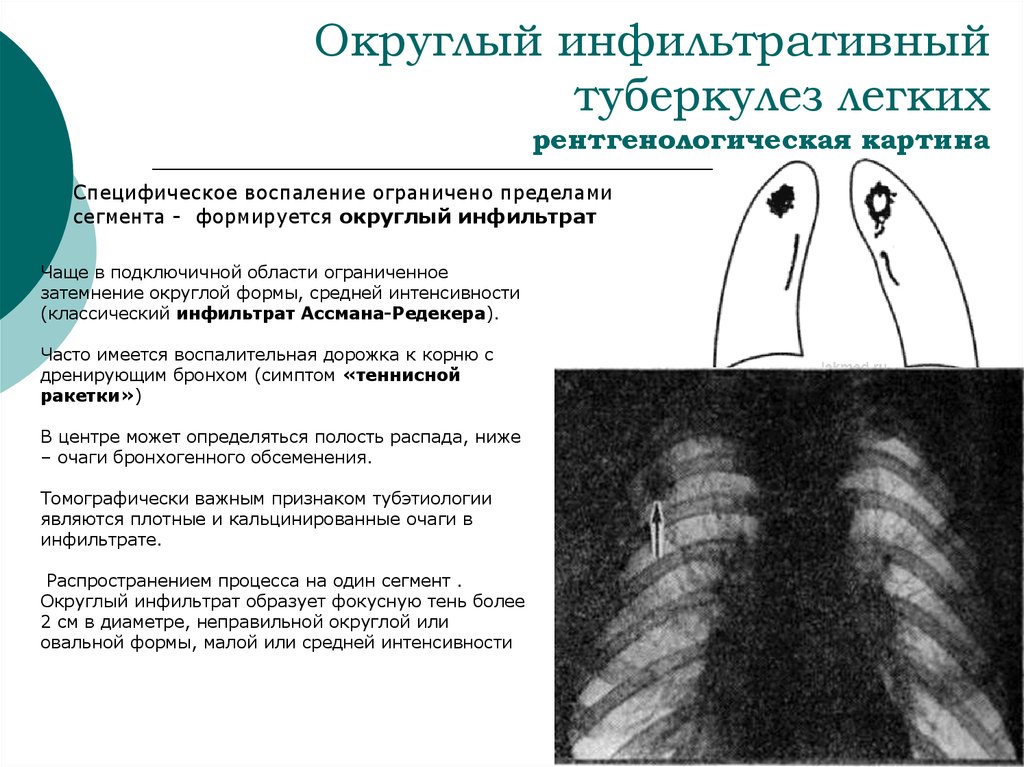

Симптомы и лечение инфильтративного туберкулеза легких

Раздел: Снимки-откровения